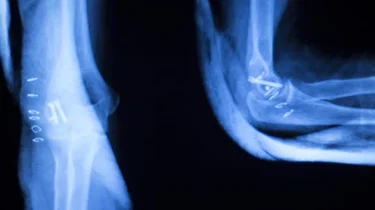

CT-scanning bliver brugt til undersøgelse af hele kroppen. Den kan fx vise komplicerede brud på knogler, forandringer i knogler eller led, blødninger og svulster, sygdomme i indre organer, betændelsestilstande og nyresten.

CT-scanning er en forkortelse for ComputerTomografi-skanning. Tomografi betyder tværsnitsundersøgelse af kroppen. Det er en avanceret røntgenundersøgelse, der giver mere detaljerede tværsnitsbilleder af kroppens forskellige væv og organer. Endvidere kan der på baggrund af de indsamlede data også laves tredimensionelle billeder.